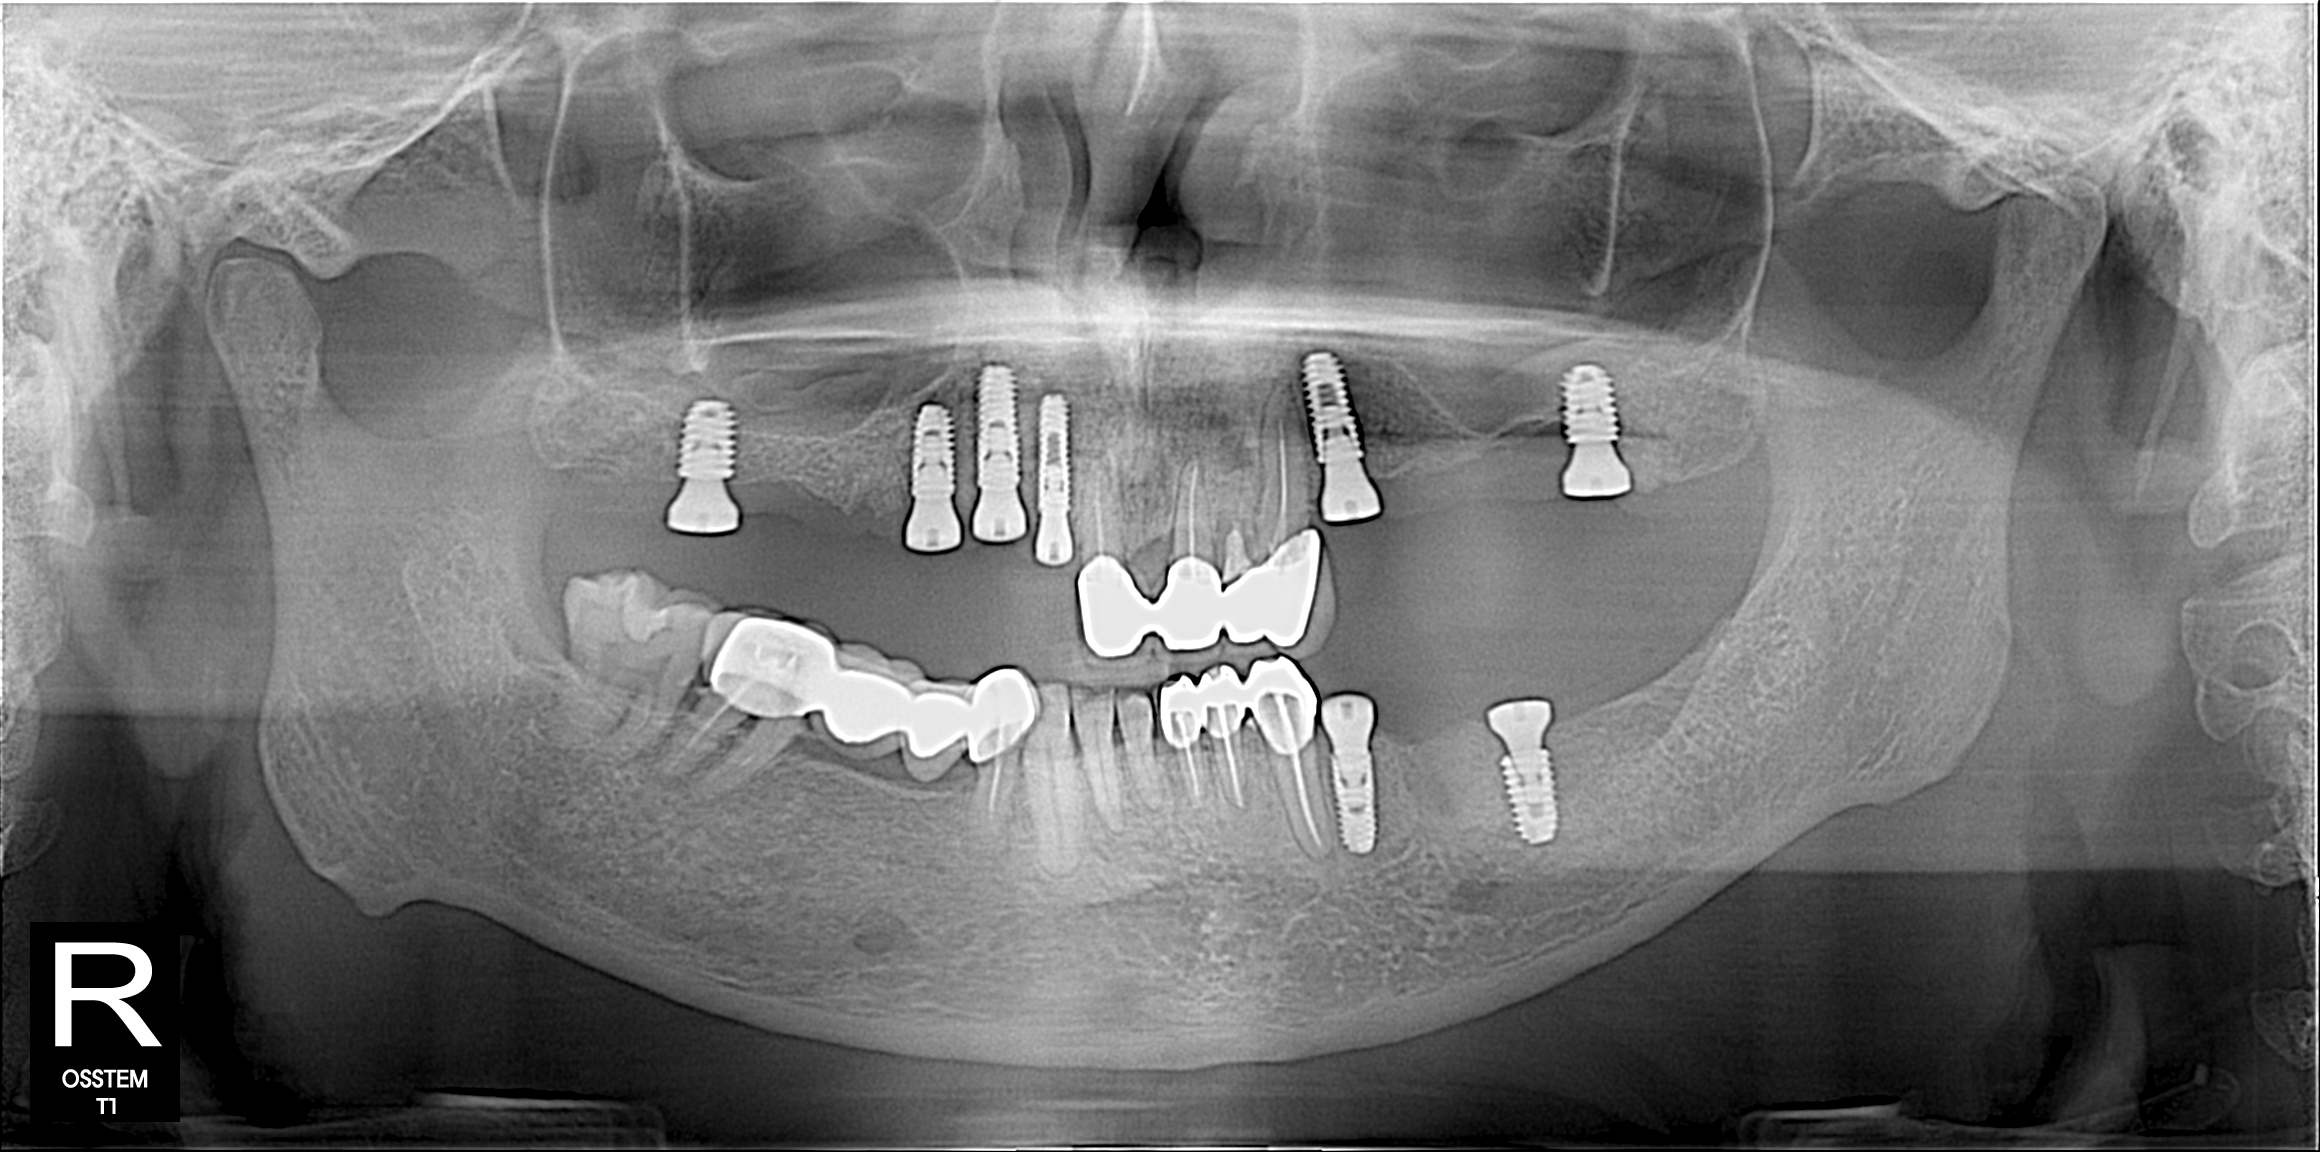

Full mouth rehabilitation with implant supported bridge or denture always challenging. We have well trained surgical team lead by Dr Rahman and specialist prosthetic team to maintain up to mark quality and gaining chewing function. Options are All on 4 , Implant retained bridges and snap on denture.

Implant Gallery